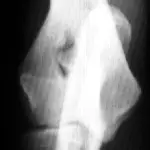

A radiograph shows a lateral view of a canine elbow joint, highlighting a fracture in the humeral condyle. The surrounding soft tissue appears normal, and there is no evidence of joint effusion.

Figure 4B. A hairline intercondylar fracture (arrow) can be seen after repositioning the elbow and x-ray beam only slightly. This may represent incomplete ossification or a true fracture. In this case, the hairline fracture was confirmed by bone scan and arthroscopy.